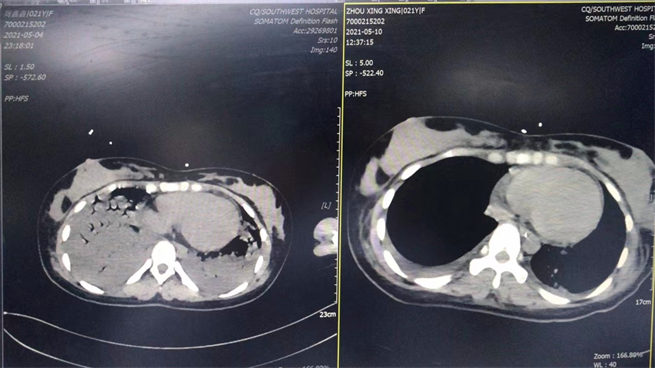

5月4日是剛轉(zhuǎn)進科時和5月10日是撤ecom后做的CT對比圖。西南醫(yī)院供圖!

當(dāng)?shù)蒯t(yī)院全力救治但病情仍持續(xù)加重,小嫣被迅速轉(zhuǎn)入了西南醫(yī)院心內(nèi)科。入院時,小嫣已經(jīng)意識喪失、嚴重休克,需要氣管插管呼吸機維持呼吸、血壓也需要去甲腎上腺素維持,心肌酶譜提示心肌鈣蛋白飆升數(shù)十倍、心臟超聲發(fā)現(xiàn)心臟收縮泵功能嚴重下降。初步判斷考慮為:暴發(fā)性心肌炎、心力衰竭、心源性休克!

小嫣就是因為暴發(fā)性心肌炎、全心衰竭,出現(xiàn)了血壓和呼吸難以維持、無尿、意識喪失,反復(fù)的室早、室顫等癥狀。如果沒有得到積極有效的治療,她將會有生命危險。